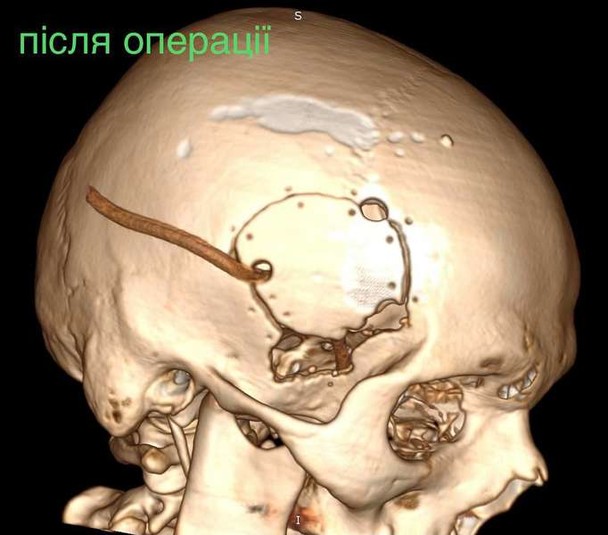

Куля зупинилась у сантиметрі від надзвичайно важливої судини

За словами нейрохірурга, підлітку провели невідкладну операцію та вилучили стороннє тіло, видалили пошкоджені тканини і відновили цілісність збережених тканин. На щастя, куля зупинилась у сантиметрі від надзвичайно важливої судини і права скронева частка (яка пошкодилась в результаті травми) – функціонально незначима.